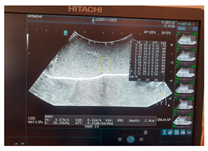

- Criteria 4: optimal characteristics for ultrasound—how optimal/not optimal is the model for ultrasound examination;

- Criteria 5: optimal characteristics for elastography—how optimal/not optimal is the model for ultrasound elastography;

- Criteria 6: optimal characteristics for Fibroscan—how optimal/not optimal is the model for Fibroscan examination;

3. Results